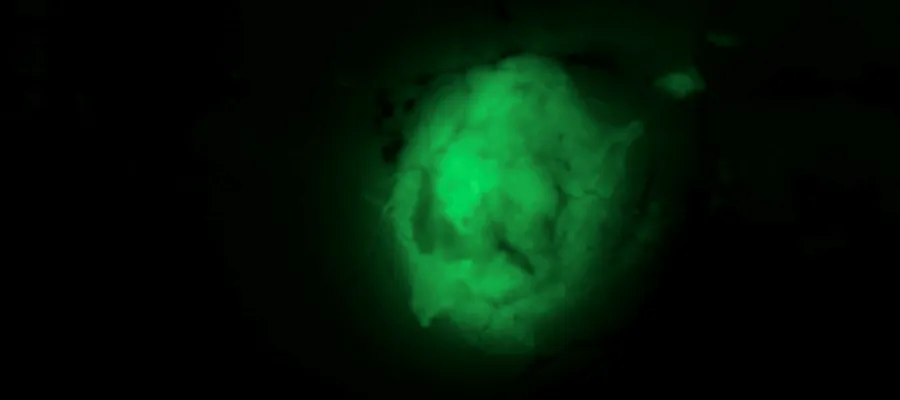

Image of an engineered glioblastoma tagged with a green fluorescent probe

Engineered glioblastoma tagged with a green fluorescent probe. Credit: Neza Alfazema